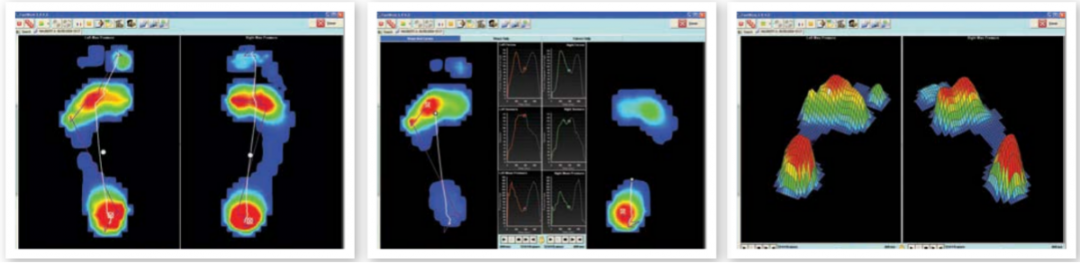

平板式足底压力分布采集分析系统

美国SPI平板式足底压力分布采集分析系统从遍布传感器板的数千个微小的压电电阻元件中捕捉足部压力变化。就像站在秤上一样,传感器板记录了现场压力和压力的临界分布模式。

可以用于静态、动态足底状况和身体平衡能力的分析,被广泛应用于运动生物力学研究、运动鞋设计、步态分析、平衡分析,糖尿病足的测试、下肢骨关节疾病等临床及科研领域。

步态数据会以多种方式显示,包括:曲线图、压强分布图形、表格以及图表,以便能快速的识别不对称性、异常与**结果,另外透过数据库,可以协助追踪**成效与比较各时期档案。